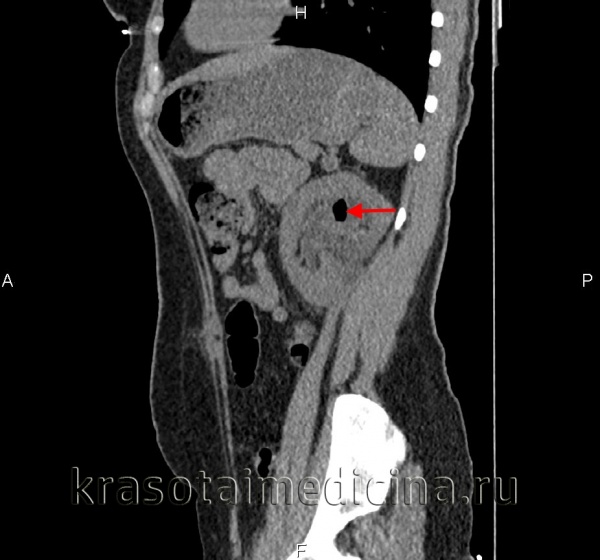

(Справа) Бесконтрастная КТ, коронарная проекция: у данного пациента обнаружен кортикальный рубец в верхнем полюсе правой почки, ассоциированный с кальцификацией небольших размеров. При хроническом пиелонефрите рубцы обычно локализуются на полюсах почки (чаще на верхних).